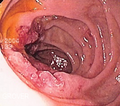

Gross

- Mass ulcerating or exophytic.

Image: